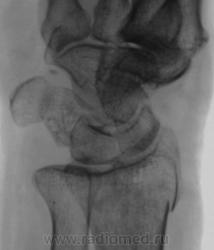

Травма.   Пациент направлен на рентгенографию лучезапястного сустава.

СЛУЧАЙ № 2.